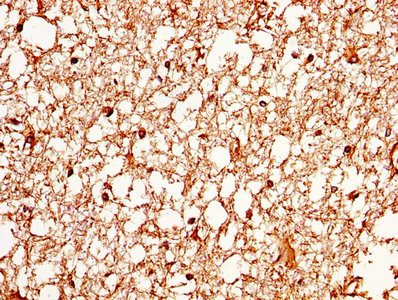

• IHC image of CSB-PA11137A0Rb diluted at 1:370 and staining in paraffin-embedded human brain tissue performed on a Leica BondTM system. After dewaxing and hydration, antigen retrieval was mediated by high pressure in a citrate buffer (pH 6.0). Section was blocked with 10% normal goat serum 30min at RT. Then primary antibody (1% BSA) was incubated at 4°C overnight. The primary is detected by a biotinylated secondary antibody and visualized using an HRP conjugated SP system.